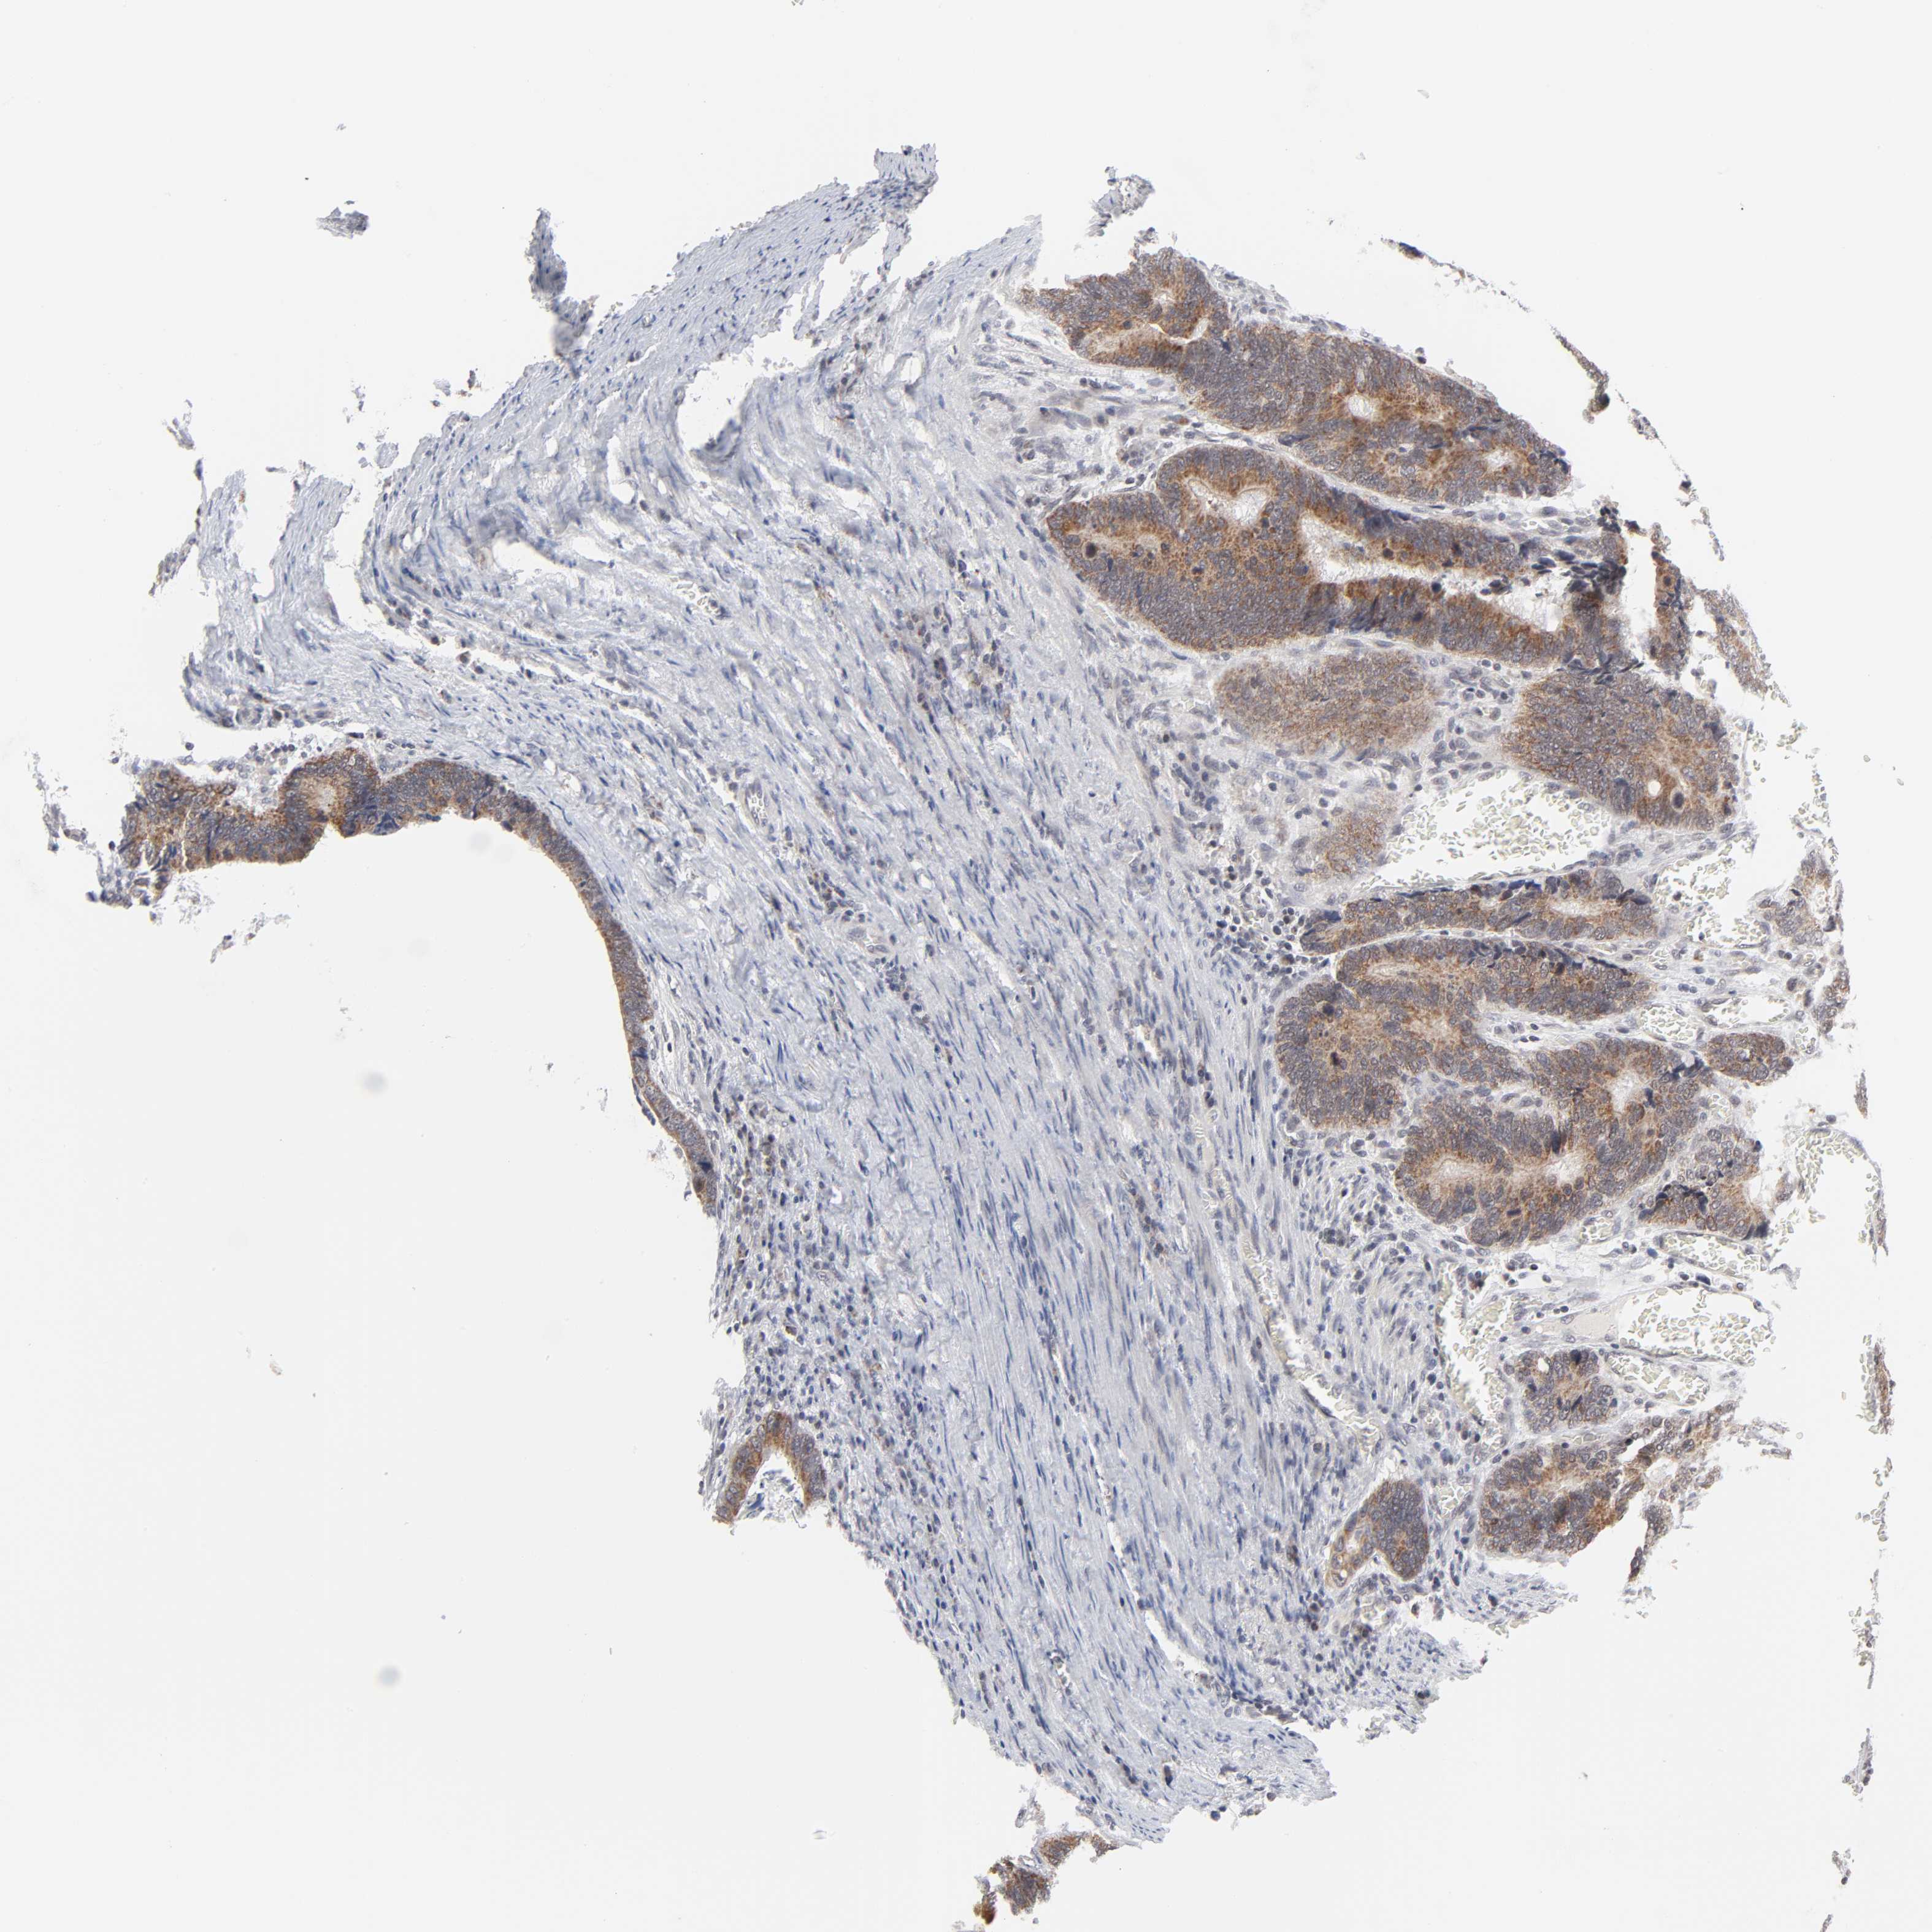

CANCER COLORECTAL CANCER Show tissue menu

Colorectal cancer

Human cancer

Colon adenocarcinoma